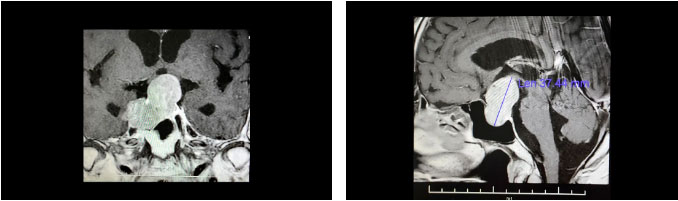

鞍区MRI平扫+增强显示,蝶鞍显著扩大,鞍底下陷,见一团块状异常信号灶,超蝶鞍生长,鞍膈处见“腰征”,瘤体轮廓尚清;肿块矢横高径约 3.7 × 4.5 × 3.7cm。病变向鞍上生长,占据鞍上池,推移视交叉上抬、分界模糊;向下生长,破坏鞍底,嵌入蝶窦内;向鞍旁生长,侵及两侧海绵窦,右侧海绵窦包裹1/2、分界欠清。

▲ 影像显示垂体占位,侵犯蝶窦及海绵窦